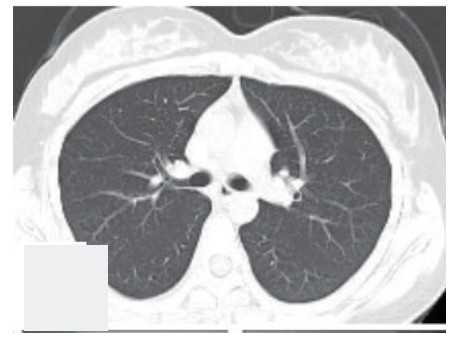

1 病例资料病例1:患者,女性,14岁,因“气急2 h”于2019-6-29入院。患者于2019年6月29日在杭州某医院行全麻下妇科手术,手术过程顺利,术中补液1 L(100 min输注500 mL胶体液+500 mL晶体液)。术后患者苏醒拔除气管插管,术后返回病房。拔管后0.5 h患者突发持续2 min的喉鸣和呃逆,之后迅速出现胸闷气急,血氧饱和度进行性下降到72%,伴有咯大量粉红色泡沫痰。立即予以高流量吸氧、速尿20 mg静注、西地兰0.2 mg静注治疗,8 min后症状略有所好转,血氧饱和度上升到97%,立即转送本院。体格检查:体温36.2℃,血压101/57 mmHg(1 mmHg=0.013 kPa),脉搏120次/min,呼吸22次/min。口唇不发绀,右肺叩诊浊音,双肺呼吸音粗,右下呼吸音低,右肺闻及较多细湿啰音;心率120次/min,律齐,无杂音;下肢无水肿。血白细胞4.7×109/L,中性粒细胞86.9%,血红蛋白155 g/L,C反应蛋白1 mg/L;N端脑钠肽前体(NT-proBNP)255 pg/mL;血浆乳酸5.4 mmol/L;生化:白蛋白34.7 g/L, 球蛋白19.3 g/L,余正常。胸部CT显示两肺大片渗出及实变影,以右肺为主,伴有右上叶小叶间隔增厚(见图 1)。入院诊断:负压性肺水肿。入院后予以速尿20 mg静注一次和甲基强的松龙40 mg静注一次,同时高流量吸氧,患者术后第2天后症状明显改善,术后第3天完全消失,术后第4天复查肺部CT病灶完全吸收(见图 2)。

| 病灶完全吸收 图 2 病例1患者术后第4天复查胸部CT |